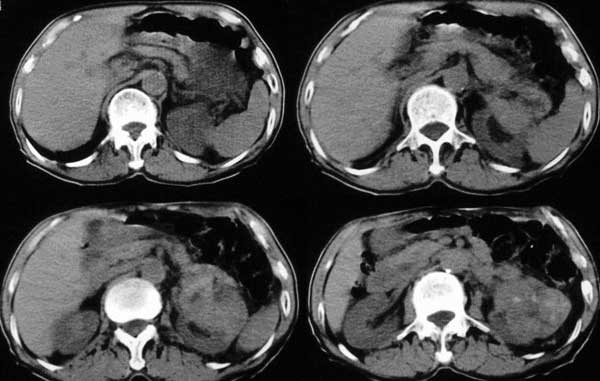

附肾脏平扫及增强片

双肺多发结节状影,腹膜后见肿大淋巴结,支持肾ca转移

支持肺内,椎体,肋骨,腹膜后淋巴转移.

手术是怎么做的,好像没做。右肾还有两个病灶。气管腔内的那个结节密度确实很低,考虑粘痰核应该没问题,若是新生物不会这么低。不过挂在前壁上了,少见!

肺及胸膜下多发结节影,胸椎及附件、肋骨破坏支持转移癌。气管内结节影支持痰核。肾脏ct应该是术前的吧?左肾内亦见一低密度灶,另外胰腺好像也不规则。不知术后结果如何?

左侧肾癌,腹膜后淋巴转移,肺及胸椎转移,右肾转移可能,气管内痰栓可能[壁可见]

左侧肾癌伴腹膜后淋巴结、胸椎、双肺内转移。